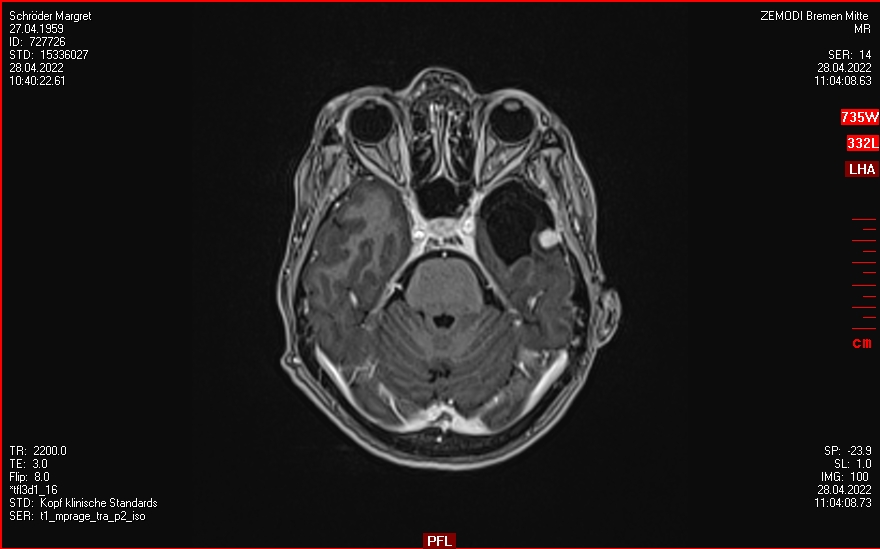

2019-2020

Ein Rezidiv wächst langsam

Die Tumorkonferenz vom Krankenhaus Bremen-Mitte rät zum Abwarten.

Der beratende Arzt dort, findet eine Bestrahlung im Gamma-Knife nicht falsch.

21.01.2021

Gamma-Knife Bestrahlung im ICERA Hamburg.